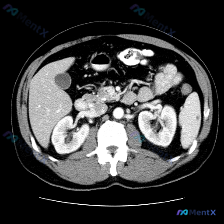

整理了一份很有意思的读片病例,差点被最初的提问带偏,分享一下思路: 病例背景 核心提问是“这张图里脾脏有什么病变?”,先来看影像的客观描述。 关键影像信息(增强CT横断面) 1. 扫描层面与质量:上腹部增强,对比度好,结构清。 2. 我们重点看的脾脏:边缘轮廓大致正常,未见明确局灶性低密度、高强化或...